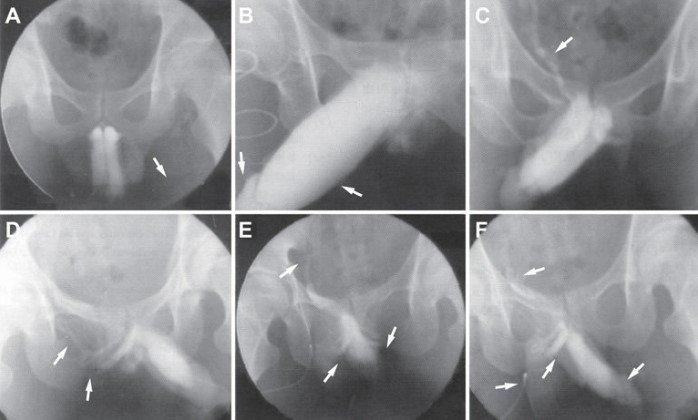

Венозная утечка в кавернозных телах, исследованная с помощью кавернозографии, показывает разные типы утечки: (A) поверхностная венозная утечка; (B) глубокая венозная утечка; (C) краральная венозная утечка; (D) кавернозная утечка; (E) венозная утечка между половым членом и уретрой; (F) смешанная венозная утечка.

Венозная утечка кавернозных тел

Венозная утечка из кавернозных тел, исследованная с использованием обычной кавернозографии, выявляет различные виды утечек: (A) Тип I: поверхностная венозная утечка (визуализация левой наружной подвздошной вены); (B) Тип II: средняя венозная утечка (визуализация уретры и головки полового члена); (C) Тип II: средняя венозная утечка (визуализация правой внутренней подвздошной вены); (D) Тип III: глубокая венозная утечка (визуализация глубоких вен полового члена); (E) Тип IV: смешанная венозная утечка (визуализация левой внутренней подвздошной вены и глубоких вен полового члена).